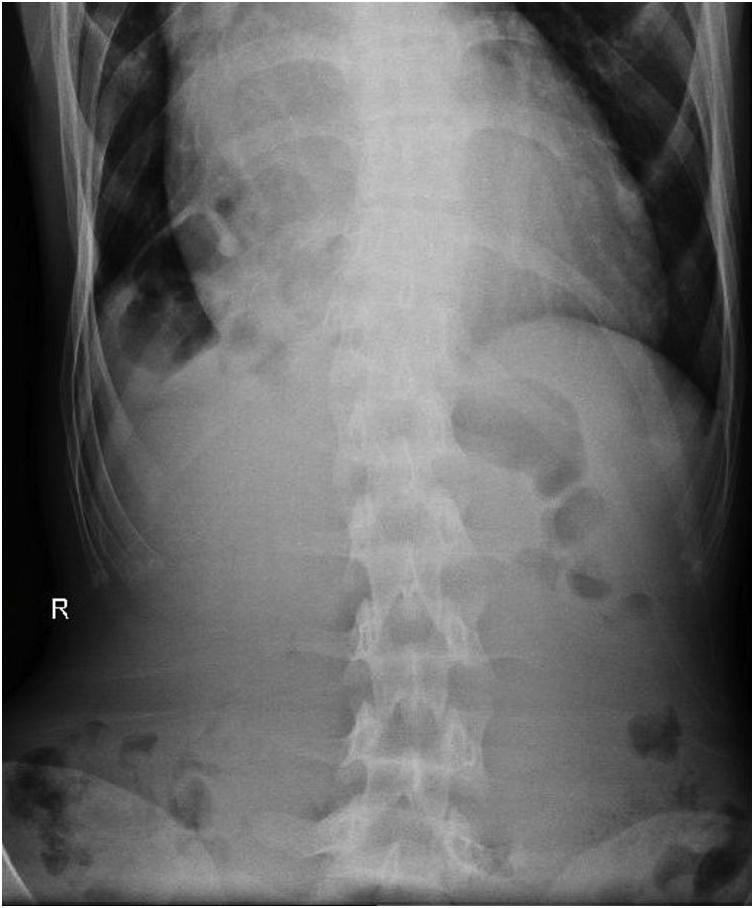

A 25-year-old female presented in the emergency room with 1 week history of abdominal discomfort. At time of examination, she had a mild shortness of breath that was not related with rigorous activities. A plain abdominal x-ray was suggested the presence of an air-filled bowel tract within the right subphrenic space (Fig. 1). Abdominal computed tomography suggested colonic loop present between the right hemi-diaphragm and liver. The absence of abdominal free air confirmed an isolated pseudo-pneumoperitoneum due to colonic interposition between the liver and diaphragm.

Chilaiditi sign is radiolucency in the subdiaphragmatic space as a result of bowel interposition between a diaphragm and the liver. If gastrointestinal symptoms present, the condition is known as Chilaiditi's syndrome. The abdominal symptoms including severe pain, anorexia, diarrhea, nausea, vomiting, bloating and constipation might mislead physicians or surgeons with diaphragmatic hernia, subdiaphragmatic abscess, bowel perforation, infected hydatid cyst and liver tumor. Thorough physical examination, imaging, and timely follow up is very important to avoid unnecessary exploratory laparotomies.

Chilaiditi's Syndrome is often misdiagnosed with bowel perforation because the presence of pseudopneumoperitoneum in the plain X-Rays. It is important to understand the unique characteristics of the sign, symptoms and findings of Chilaiditi's Syndrome to prevent unnecessary surgical procedures.